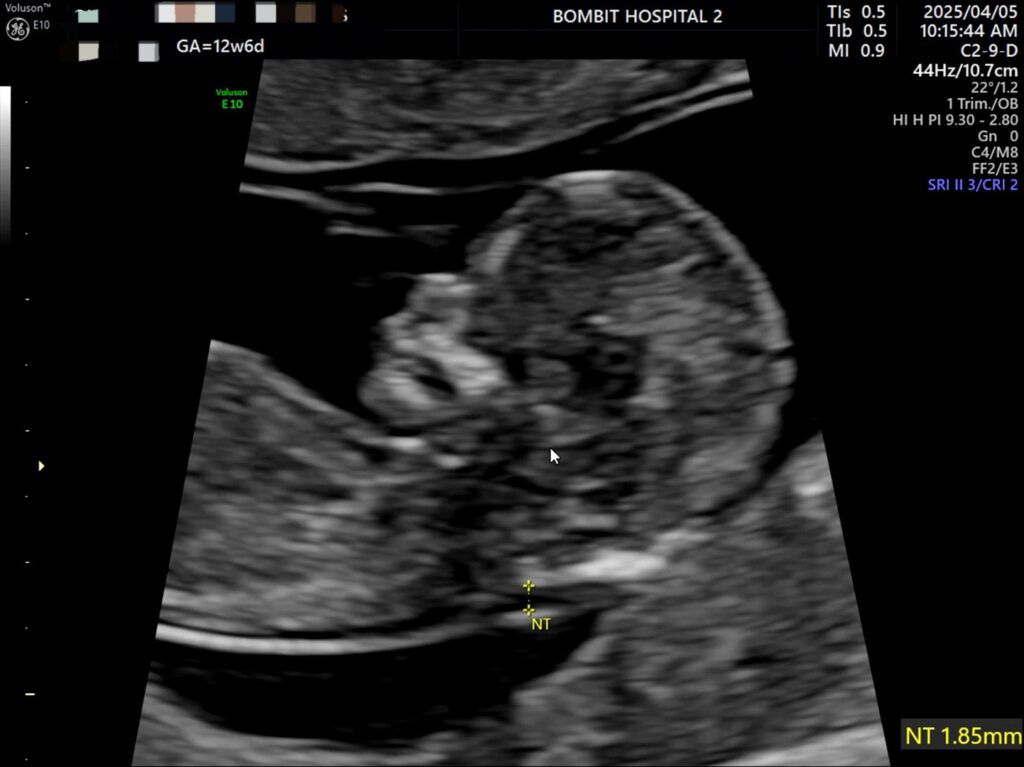

봄빛병원에 다시 방문. 정밀초음파도 하고, 다시 진료도 보았다.

피고임은 이제 없어졌다고 했다. 약간은 느려진 듯한 심장소리도 다시 들었고 니프티 검사용 채혈도 했다.

정밀초음파 사진.